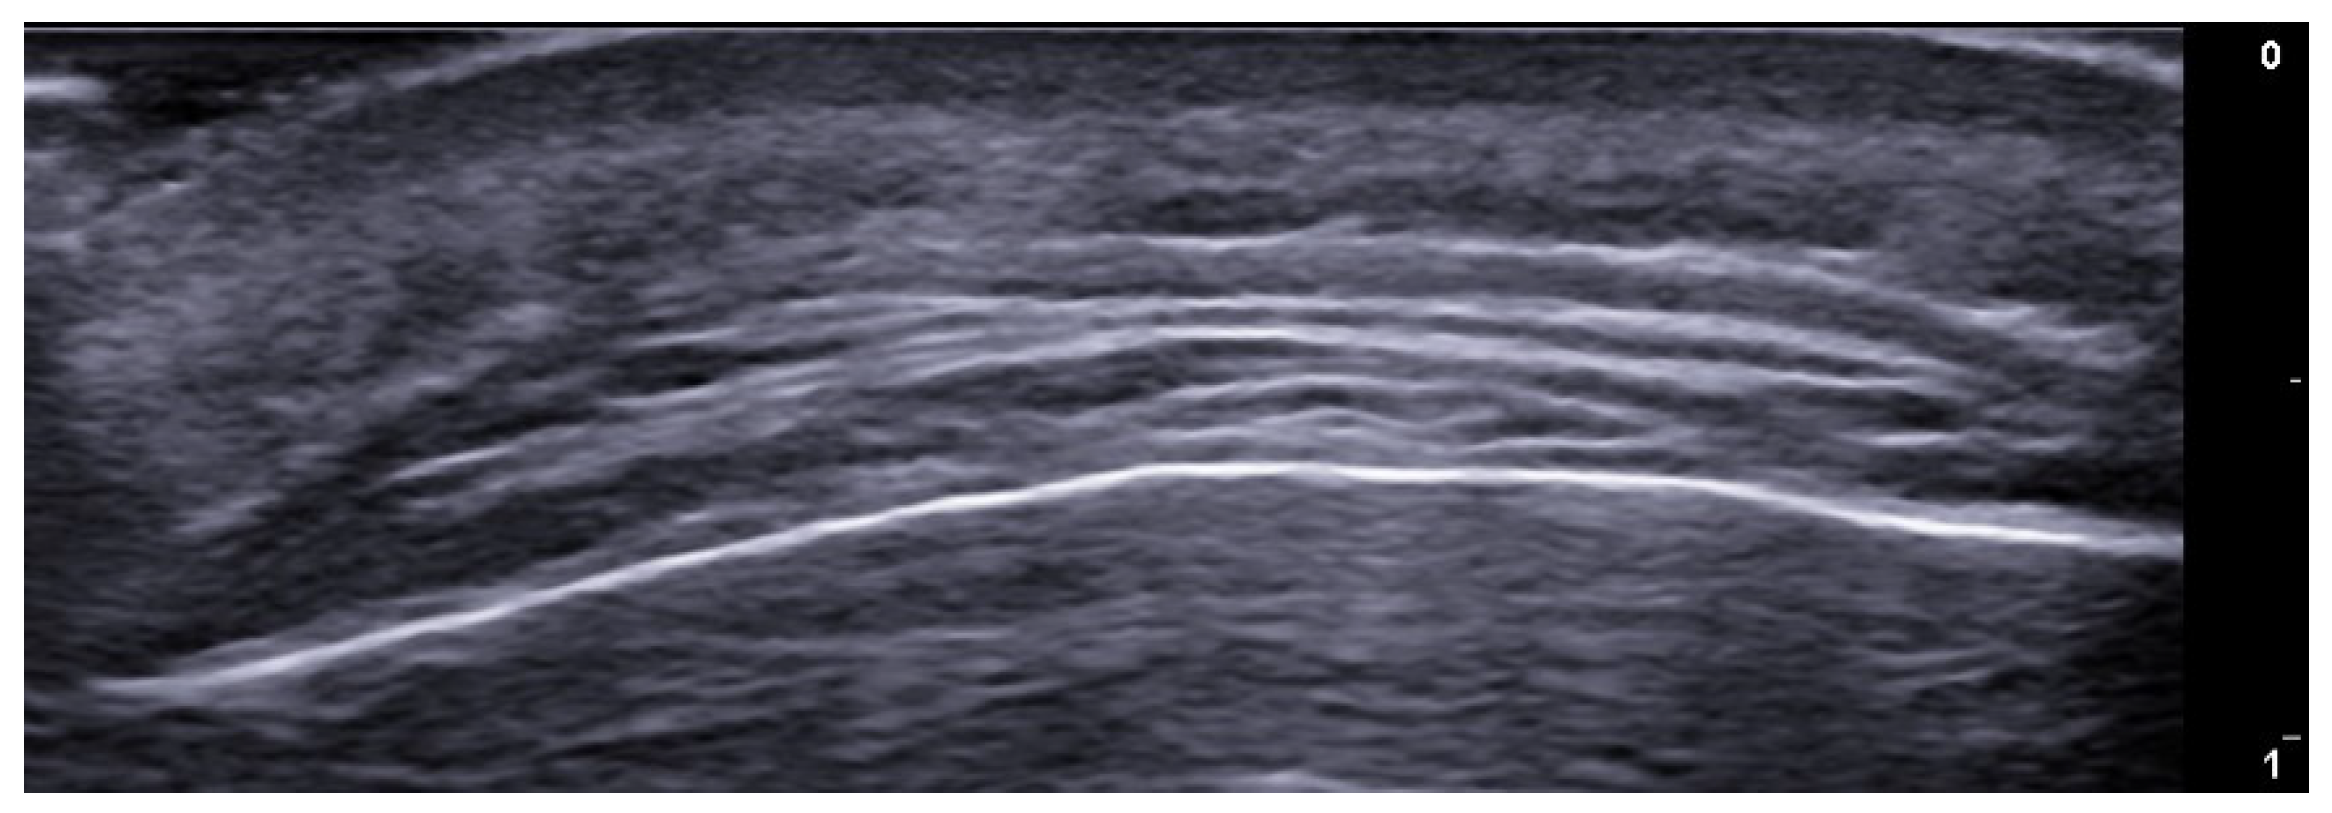

2. Infections

3. Inflammatory Dermatoses

4. Metabolic and Genetic Disorders

5. Specific Cutaneous Structure and Sites of Skin Disorders

6. Vascular Disorders

7. External-Agent-Associated Disorders

8. Neoplastic Diseases

9. Aesthetic Medicine